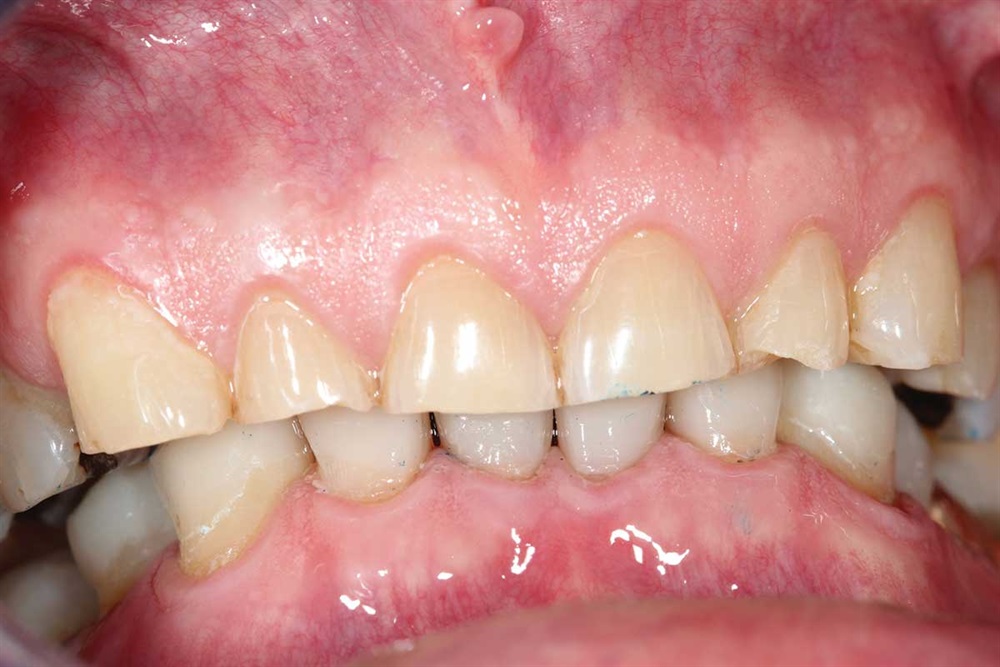

Fig. 14–16: It is hard to see, but the patient’s bicuspids nearly miss in occlusion because the upper bicuspids are buccal to his lower bicuspid. One reason for ortho would have been to expand the lower arch to get more occlusion on the bicuspids.

Fig. 15

Fig. 16